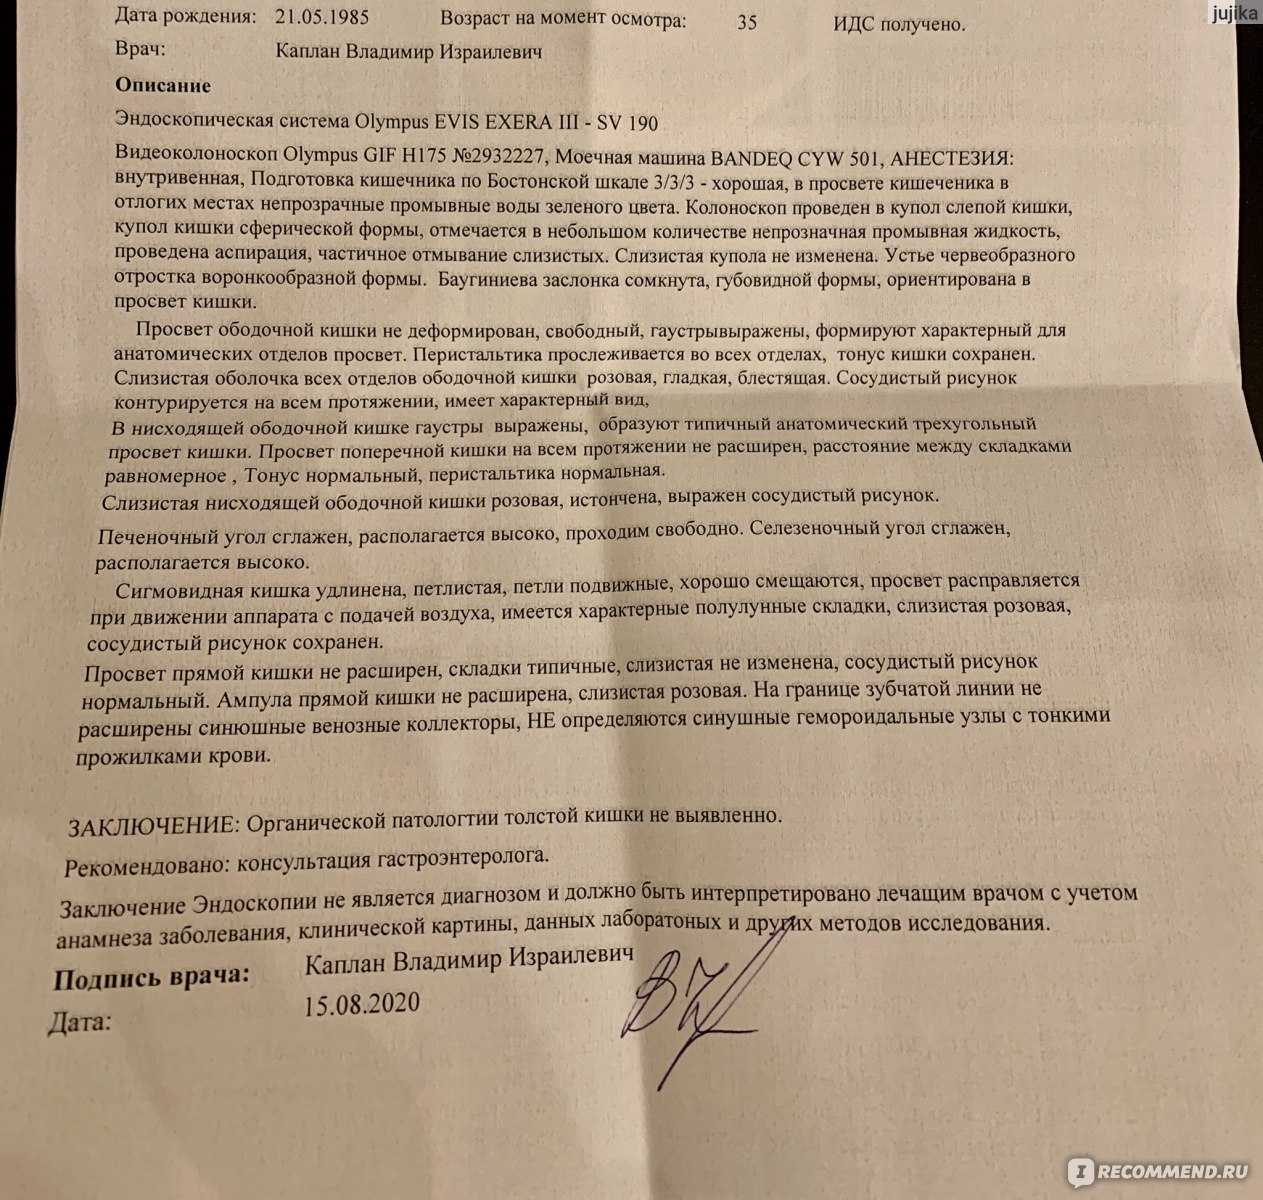

Подготовка к ирригоскопии: необходимые препараты